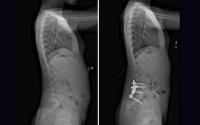

Dr. Vitale and Dr. Oh recently completed a complex case together, successfully performing a hemivertebrectomy and posterior spinal fusion in an 11-year-old with progressive congenital scoliosis with a L5 hemivertebra. The hemivertebra, which caused 70 degrees of scoliosis, needed to be excised and the spine fused, so Dr. Vitale and Dr. Oh devised a surgical plan that involved Dr. Oh performing the hemivertebrectomy and Dr. Vitale performing the spinal fusion.

Dr. Vitale and Dr. Oh collaborated on a surgery to correct progressive congenital scoliosis with a L5 hemivertebra. Together, they performed a hemivertebrectomy and posterior spinal fusion to remove the vertebra and correct the patient’s spinal alignment.

The procedure was successful; the patient has experienced dramatic improvement in her spinal alignment and deformity and has resumed her normal activities, including gymnastics.